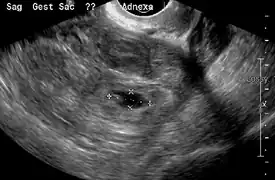

An ultrasound showing a gestational sac with fetal heart in the fallopian tube has a very high specificity of ectopic pregnancy. Transvaginal ultrasonography has a sensitivity of at least 90% for ectopic pregnancy.[4] The diagnostic ultrasonographic finding in ectopic pregnancy is an adnexal mass that moves separately from the ovary. In around 60% of cases, it is an inhomogeneous or a noncystic adnexal mass sometimes known as the "blob sign". It is generally spherical, but a more tubular appearance may be seen in case of hematosalpinx. This sign has been estimated to have a sensitivity of 84% and specificity of 99% in diagnosing ectopic pregnancy.[4] In the study estimating these values, the blob sign had a positive predictive value of 96% and a negative predictive value of 95%.[4] The visualization of an empty extrauterine gestational sac is sometimes known as the "bagel sign", and is present in around 20% of cases.[4] In another 20% of cases, there is visualization of a gestational sac containing a yolk sac or an embryo.[4] Ectopic pregnancies where there is visualization of cardiac activity are sometimes termed "viable ectopic".[4]

Ultrasound image showing an ectopic pregnancy where a gestational sac and fetus has been formed.